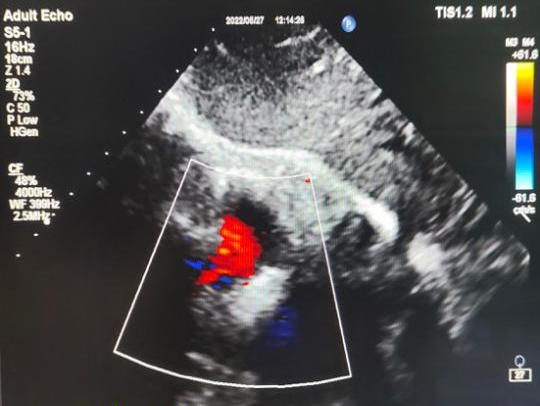

术后超声